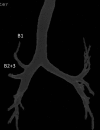

A 69-year-old woman visited our hospital complaining of right chest pain. Chest computed tomography showed a 55 × 45 mm tumor in the right upper lobe. Bronchoscopy revealed displaced anomalous B 1 and B 2+3 arising from the right main bronchus, and the patient was diagnosed with lung adenocarcinoma by transbronchial lung biopsy from the displaced B 2+3 . Three-dimensional computed tomography with multiplanar reconstruction revealed a displaced anomalous B 1 and B 2+3 branching directly from the right main bronchus, respectively, and abnormal distribution of the aberrant pulmonary vein (V 2 ) descended dorsally to the right main bronchus and emptied into the left atrium. Video-assisted right upper lobectomy with nodal dissection was successfully performed. Attention should be paid to the anomalous bronchus and pulmonary vessels for safer lung cancer operations, especially for video-assisted thoracic surgery.